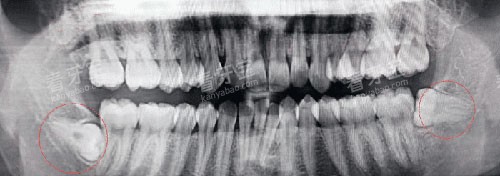

反复发作的智齿冠周炎(每年发作≥3次)。

智齿本身龋坏且已波及牙髓。

阻生智齿压迫邻牙导致牙根吸收。

智齿引发颌骨囊肿或含牙囊肿。

简单智齿(已萌出、位置正):优先选择社区医院。

复杂阻生齿(未萌出、靠近神经管):建议综合医院口腔颌面外科。